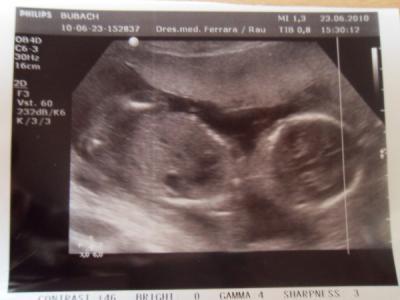

Hallo ihr lieben, habe leider im Moment eine Blasenentzüngung. Wir waren am Freitag Abend schonmal im Krankenhaus. Leider hat das Penicillin nicht geholfen Da wurd schon ein US gemacht. Leider meinte die Ärztin sie kann nichts sehen, es wäre zu verschwommen zwischen den Beinen . Mein Mann meinte er hätte es gesehen, da wollte ich es aber noch nicht glauben. Heute hatte ich wieder schlimme Probleme beim Wasserlassen. Also ab zum FA. Diesmal hatte ich sogar Blut im Urin. Er hat liebenswürdigerweise ein US gemacht. Und jaaaa mein Mann hatte wohl recht. Der Arzt meint auch das er sagt das es wohl ein Mädchen wird. Er sei sich aber nicht ganz sicher. Aber 80% gibt er mir :D Wir sind so gespannt ob unser Sohn eine kleine Schwester bekommt. Nächsten Mittwoch hab ich ja den zweiten großen Ultraschall Termin. Mal sehen ob es der Vertretungsarzt (meiner fährt jetzt in Urlaub) nochmal bestätigt. wünsche euch mitkugelnden alles liebe lg Steffi

Bild zu War außerplanmäßig beim FA. 80%iges Outing :D - Forum für November - Mamis